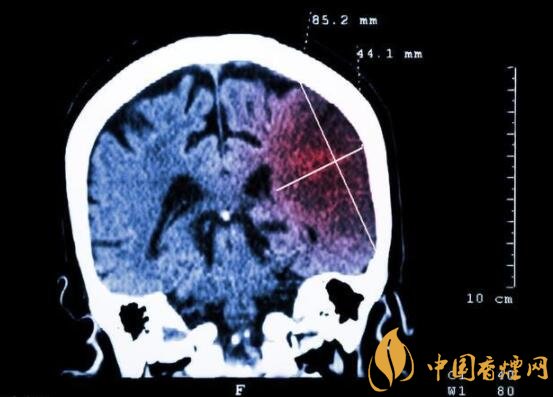

一般而言,急性腦梗塞與長期吸煙有非常密切的聯(lián)系。有長期煙齡遇到肢體活動(dòng)不順,做頭顱核磁共振檢查往往查出一側(cè)大腦中動(dòng)脈閉塞的可能性很高。由此可見,吸煙確實(shí)與中風(fēng)存在一定聯(lián)系。

在這當(dāng)中,吸煙者與不吸煙者做對比,發(fā)生中風(fēng)時(shí)間可提前十年。按照每日吸煙1-20支,對比不吸煙者發(fā)生中風(fēng)風(fēng)險(xiǎn)高出3.3倍;每日吸煙20支以上者,比不吸煙者高出5.6倍;30-40歲吸煙者,發(fā)生腦梗塞風(fēng)險(xiǎn)比不吸煙者高出5倍;50-60吸煙者,發(fā)生腦梗塞風(fēng)險(xiǎn)比不吸煙者高出3倍。由此可見,吸煙量越大,吸煙時(shí)間越長,發(fā)生中風(fēng)的可能性越高,特別是多發(fā)生在中年